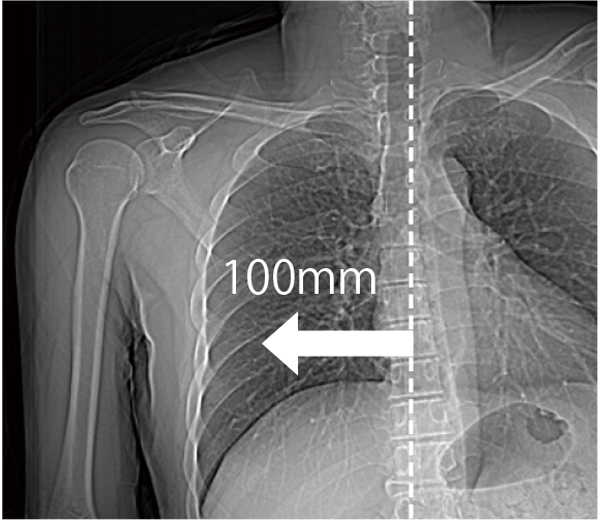

The patient table can move horizontally up to 200 mm, making it easier to position the scanned region in the center, even in cardiac or orthopedic areas, such as the shoulder. This is expected to improve examination efficiency.

Positioning the extremities near the center of the field of view